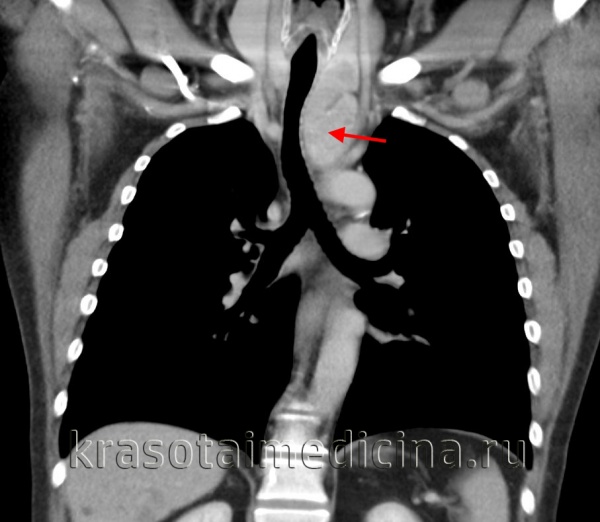

(б) Женщина 33лет, которой была выполнена КТА по поводу тромбоэмболии легочной артерии.

При сканировании в правой паравертебральной области случайно было выявлено мягкотканное объемное образование, гетерогенно накапливающее контрастное вещество.

Также было обнаружено расширение межпозвонкового отверстия на уровне позвонка Th8 и распространение опухоли в спинномозговой канал. При биопсии под ультразвуковым контролем был подтвержден диагноз шванномы.